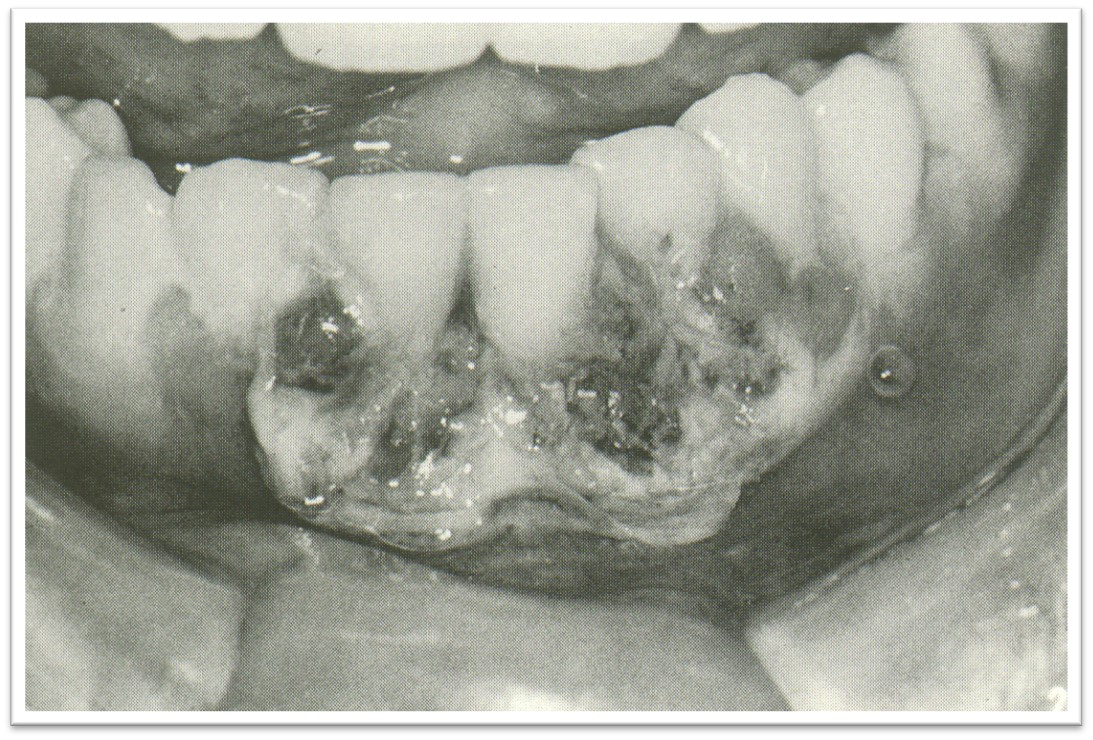

②临床表现

本病特征:龈缘及龈乳头坏死,呈蚕蚀状缺失(图10.1-6),覆盖灰白色假膜。腐败性口臭,极易出血,常突然发病,易复发,并发口炎,表现黏膜的假膜性溃疡。

图10.1-6 急性坏死性溃疡性龈炎